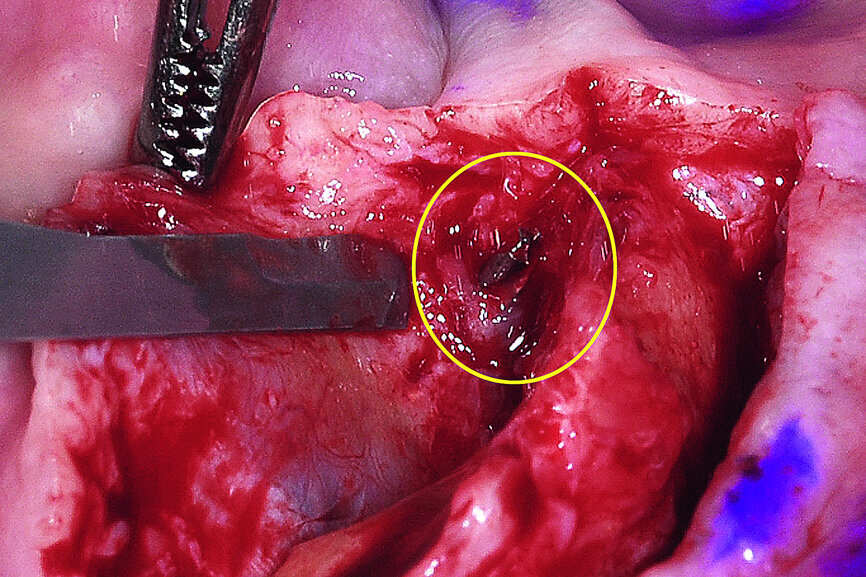

The broken drill was immediately located lingual to the alveolar crest embedded in the soft tissue. Apparently, the drill deflected off the sharp ridge into the floor of the mouth, and the torque caused the drill to break. Fortunately, the drill did not cause any immediate complications as the floor of the mouth contains many vessels, which if perforated, could have resulted in a sublingual hematoma. The remaining broken drill as seen in Figure 14 was easily retrieved.

Once the offending element was removed, the plan was to reduce the knife-edged ridge to gain appropriate width for implant placement. The reduction was accomplished in a free-hand method based upon the position and location of the mental foramen on either side of the symphysis. Based upon a thorough review of the CBCT scan data the expected hollow area of bone in the anterior symphysis was exposed (Fig. 15).

Fig. 14: The broken drill was located lingual to the bony crest of the mandible.